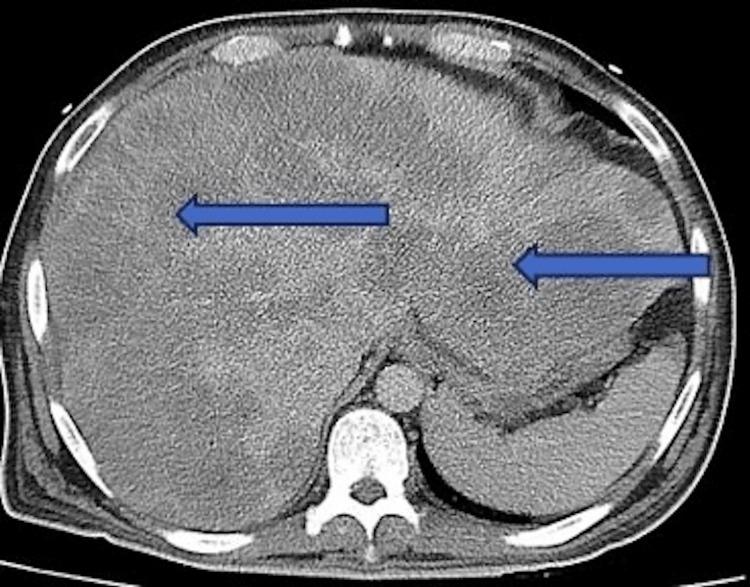

Lactic acidosis occurs from an overproduction of lactate or decreased metabolism. It is common in critically ill patients, especially those with hematological conditions such as multiple myeloma, leukemia, and lymphoma. There are two types of lactic acidosis, Type A and Type B, with Type B presenting more commonly in hematological conditions that require prompt diagnosis and treatment of the underlying condition. We present a case of a 43-year-old male with Type B lactic acidosis secondary to stage IV colon cancer with metastasis to the liver. Initial laboratory work was significant for lactic acid of 16.52 mmol/L. Arterial blood gas (ABG) showed pH 7.26, pCO 21 mmHg, pO 111 mmHg, and HCO 9 mEq/L, revealing an anion gap and metabolic acidosis with compensatory respiratory alkalosis. Initially, the patient was treated with aggressive fluid management, IV antibiotics, and sodium bicarbonate; however, his lactic acid continued to rise. The recommendation was made for urgent dialysis. Despite treatments, the prognosis is poor.

乳酸性酸中毒是由于乳酸生成过多或代谢减少所致。在危重症患者中很常见,尤其是那些患有血液系统疾病的患者,如多发性骨髓瘤、白血病和淋巴瘤。乳酸性酸中毒有两种类型,A型和B型,B型在需要及时诊断和治疗基础疾病的血液系统疾病中更为常见。我们报告一例43岁男性,继发于IV期结肠癌伴肝转移的B型乳酸性酸中毒。初始实验室检查显示乳酸水平为16.52 mmol/L,具有显著意义。动脉血气(ABG)显示pH 7.26,pCO₂ 21 mmHg,pO₂ 111 mmHg,HCO₃⁻ 9 mEq/L,提示存在阴离子间隙和代谢性酸中毒伴代偿性呼吸性碱中毒。最初,患者接受了积极的液体管理、静脉抗生素治疗和碳酸氢钠治疗;然而,他的乳酸水平持续升高。建议进行紧急透析。尽管进行了治疗,但预后很差。